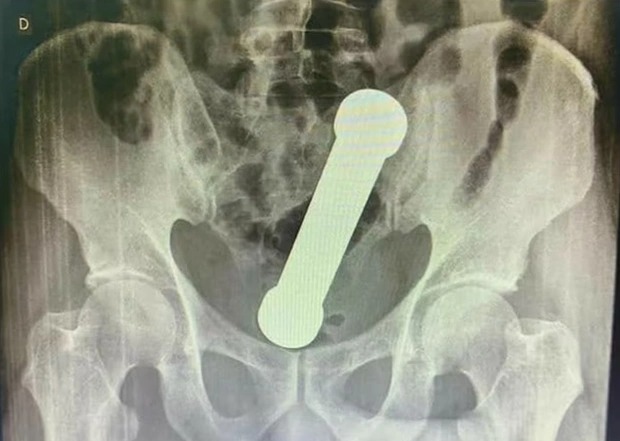

Đến khi cầm tấm phim chụp trên tay, các bác sĩ đã không khỏi hốt hoảng khi phát hiện một dị vật hình trụ dài 20cm trong cơ thể người bệnh giống như một quả tạ. Lúc này nạn nhân mới cho biết trước đó anh đã cố gắng tự mình lấy "vật thể" ra khỏi cơ thể nhưng không thành công, tuy nhiên người này không cho biết nguyên nhân trước đó có sự xuất hiện của món đồ này.

Các bác sĩ sau đó đã trấn an người bệnh và tiến hành phẫu thuật với ý định ban đầu là dùng nhíp để gắp vật thể ra tuy nhiên vì là một khối tạ kim loại nên việc này bất khả thi. Phương án cuối cùng được lựa chọn là các bác sĩ tự tay lôi "nó" ra ngoài, bệnh nhân sau đó cũng nhanh chóng hồi phục sức khỏe và xuất viện sau 3 ngày.